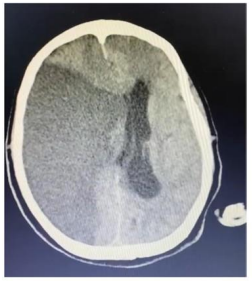

Um paciente de 76 anos de idade deu entrada na UPA, já fora de janela para trombólise, e foi posteriormente encaminhado para a UTI. A imagem apresentada refere-se à tomografia de admissão na UTI.